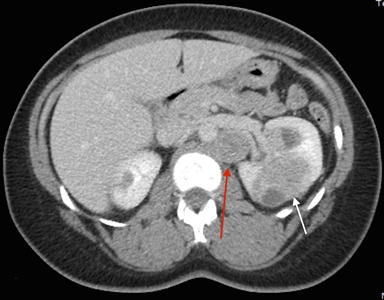

Los síntomas del cáncer de células renales (RCC) son hematuria, dolor lumbar y masa palpable. Sin embargo, muchas personas con RCC son asintomáticas. Además, no todas las personas con HLRCC presentarán RCC, ni será parte del cuadro clínico inicial. La mayoría de los RCC son unilaterales y solitarios; pero en algunas personas, son multifocales. Todavía no se ha determinado el incidencia exacta del RCC en personas afectadas, las estimaciones realizadas por diferentes grupos oscilan mucho (1–60 %).[1,3,8] La incidencia varía en función del lugar donde se realizó el estudio, las pautas de derivación de grupos individuales, y los exámenes de detección para el RCC a los que se someten los participantes. En los estudios del Instituto Nacional del Cáncer (NCI), se identificó RCC en el 32 % de las familias evaluadas.[1,3] La mediana de edad en el momento de la detección del RCC fue de 37 años,[9] aunque se notificaron algunos casos en edades tan tempranas como 10 años.[10] En otra serie grande de 135 pacientes se calculó que el riesgo de por vida fue de un 20,8 % a los 85 años de edad.[11] A diferencia de otros síndromes hereditarios de RCC, el RCC asociado a la HLRCC es muy maligno,[12,13] con un grado nuclear de Fuhrman de 3 o 4 en muchos casos; 9 de 13 personas murieron por enfermedad metastásica en el transcurso de 5 años del diagnóstico.[3] En la Figura 1 se observan varias lesiones de RCC en un paciente con HLRCC.